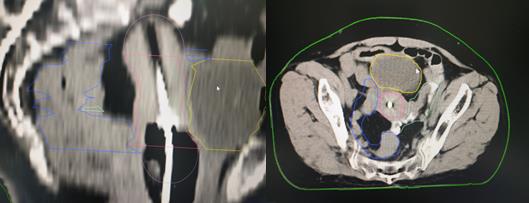

現(xiàn)代腔內(nèi)近距離放療技術(shù),即三維后裝近距離放療技術(shù),使用的放射源主要是銥192。通過(guò)先進(jìn)的計(jì)算機(jī)技術(shù),CT成像技術(shù),自動(dòng)控制技術(shù)等,實(shí)現(xiàn)三維后裝近距離放療,是一種個(gè)體化的精準(zhǔn)近距離放療技術(shù)。一般完成體外放療劑量45-50Gy后,大部分腫瘤會(huì)得到有效殺傷,但由于受到周?chē)c管及膀胱等正常器官的劑量限制,宮頸腫瘤仍未達(dá)到根治劑量,還有殘留,若此時(shí)停止治療,腫瘤很快就會(huì)復(fù)發(fā)。為進(jìn)一步提高宮頸腫瘤放療劑量,此時(shí)采用三維后裝近距離腔內(nèi)照射,將小型化療的放射源送到宮腔及宮頸腫瘤部位,對(duì)殘余腫瘤單次給予很高劑量照射,而周?chē)=M織照射劑量極速下跌,完美的實(shí)現(xiàn)高劑量殺滅腫瘤,正常組織受到較低劑量的影響,從而提高腫瘤患者的生存年限及生存質(zhì)量。